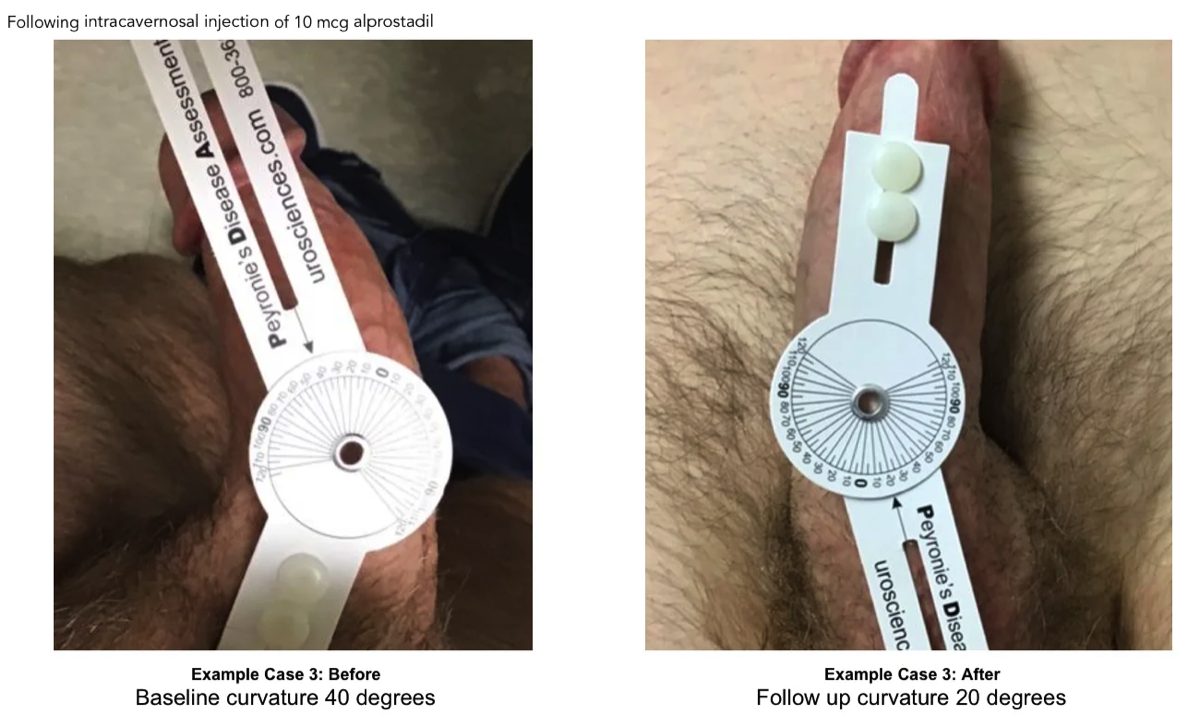

Degree of penile curvature was recorded during the initial and follow up duplex doppler ultrasound by use of a protractor. In many cases, but not all, pictures were provided with protractor showing measurement of current curve. Value of curve was accepted with or without confirmation picture.

3.2 ExoSurge treatment change in curve

A comparison was made between initial duplex doppler ultrasound and final/intra-treatment ultrasound as some patients were still undergoing treatments. Of the initial 50 patients with a curve, 36 of those patients also had a venous leak. Of the 50 patients with a curve, 17 of them had a curve less than 30 degrees with 12 of those with a venous leak. Thirty-three of the 50 had a curve greater than 30 degrees, of which 24 had a venous leak. The final study review of the 50 pts who were initially found to have a curve, 8 of those patients had no curve at all. Of the original 33 with a curve greater than 30 degrees, this number decreased to only 20 patients. On the initial study only 17 patients had a curve less than 30 degrees and this increased to 22. Therefore, 8 patients completely corrected to no longer have a curve and 5 had reduced significantly, one patient's curve increased by 8 degrees. A 58% reduction in curve was noted for the entire group who showed a decrease in the degree of curve. Fourteen percent of patients showed no improvements with the curve.

During the time reviewed, we found only 24 patients still receiving therapy at the final date for review. The individual average improvement for these patients at the end date was 60%. Of the 26 patients no longer participating in treatment, there was an individual average

Figure 3 Improvements Average Per Patient

improvement of 55% to their curvature. This change is congruent with our observations showing the largest change in curvature realized toward the end of therapy.

Before and After Peyronie's Treatment Photos

Have you ever Googled "before and after Peyronie's treatment photos"? The only images you'll find are gut wrenching photos taken midway through plication or "incision & graft" Peyronie's surgery.

Following are baseline and follow up images of Peyronie's patients following treatments with ExoSurge®. We hope to share many more soon. Unfortunately, patients must grant us permission to release these photographs, and few are willing to do that.